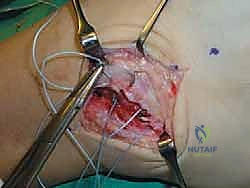

الخطوة الثالثة: تقييم التمزق وتنظيف المفصل

بمجرد الوصول إلى الكبسولة المفصلية، يتم فتحها لتقييم حالة الأربطة (ATFL و CFL). غالباً ما تكون الأربطة متندبة ومطاطية وغير قادرة على شد المفصل. يتم تنظيف أي أنسجة ملتهبة أو بقايا غضروفية حرة داخل المفصل لضمان عدم وجود ألم بعد العملية.

الخطوة الرابعة: تحضير العظم (Decortication)

لضمان التحام الأربطة بالعظم بقوة، يقوم الجراح بخدش أو تقشير الطبقة الخارجية من عظمة الشظية (Fibula) في مكان الارتكاز التشريحي للأربطة، مما يحفز النزيف العظمي الذي يجلب الخلايا الجذعية وعوامل النمو اللازمة لالتئام الأنسجة.